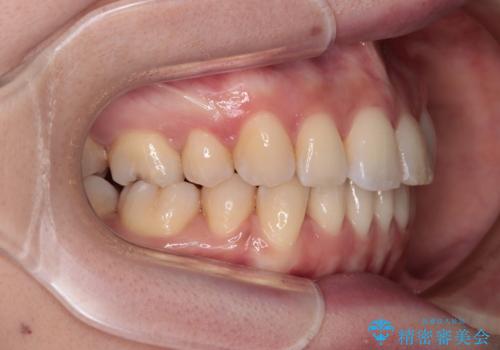

【モニター】飛び出した上顎前歯を抜歯矯正で引っ込める ワイヤー装置の抜歯矯正治療

- 口元の閉じにくさを気にして来院された患者様です。

上下ともに歯列が前方に突出していたため、上下左右の第一小臼歯4本を抜去し、ワイヤー装置による矯正治療を行うこととしました。

舌の突出癖による影響もあったため、舌のトレーニングを並行して実施しました。